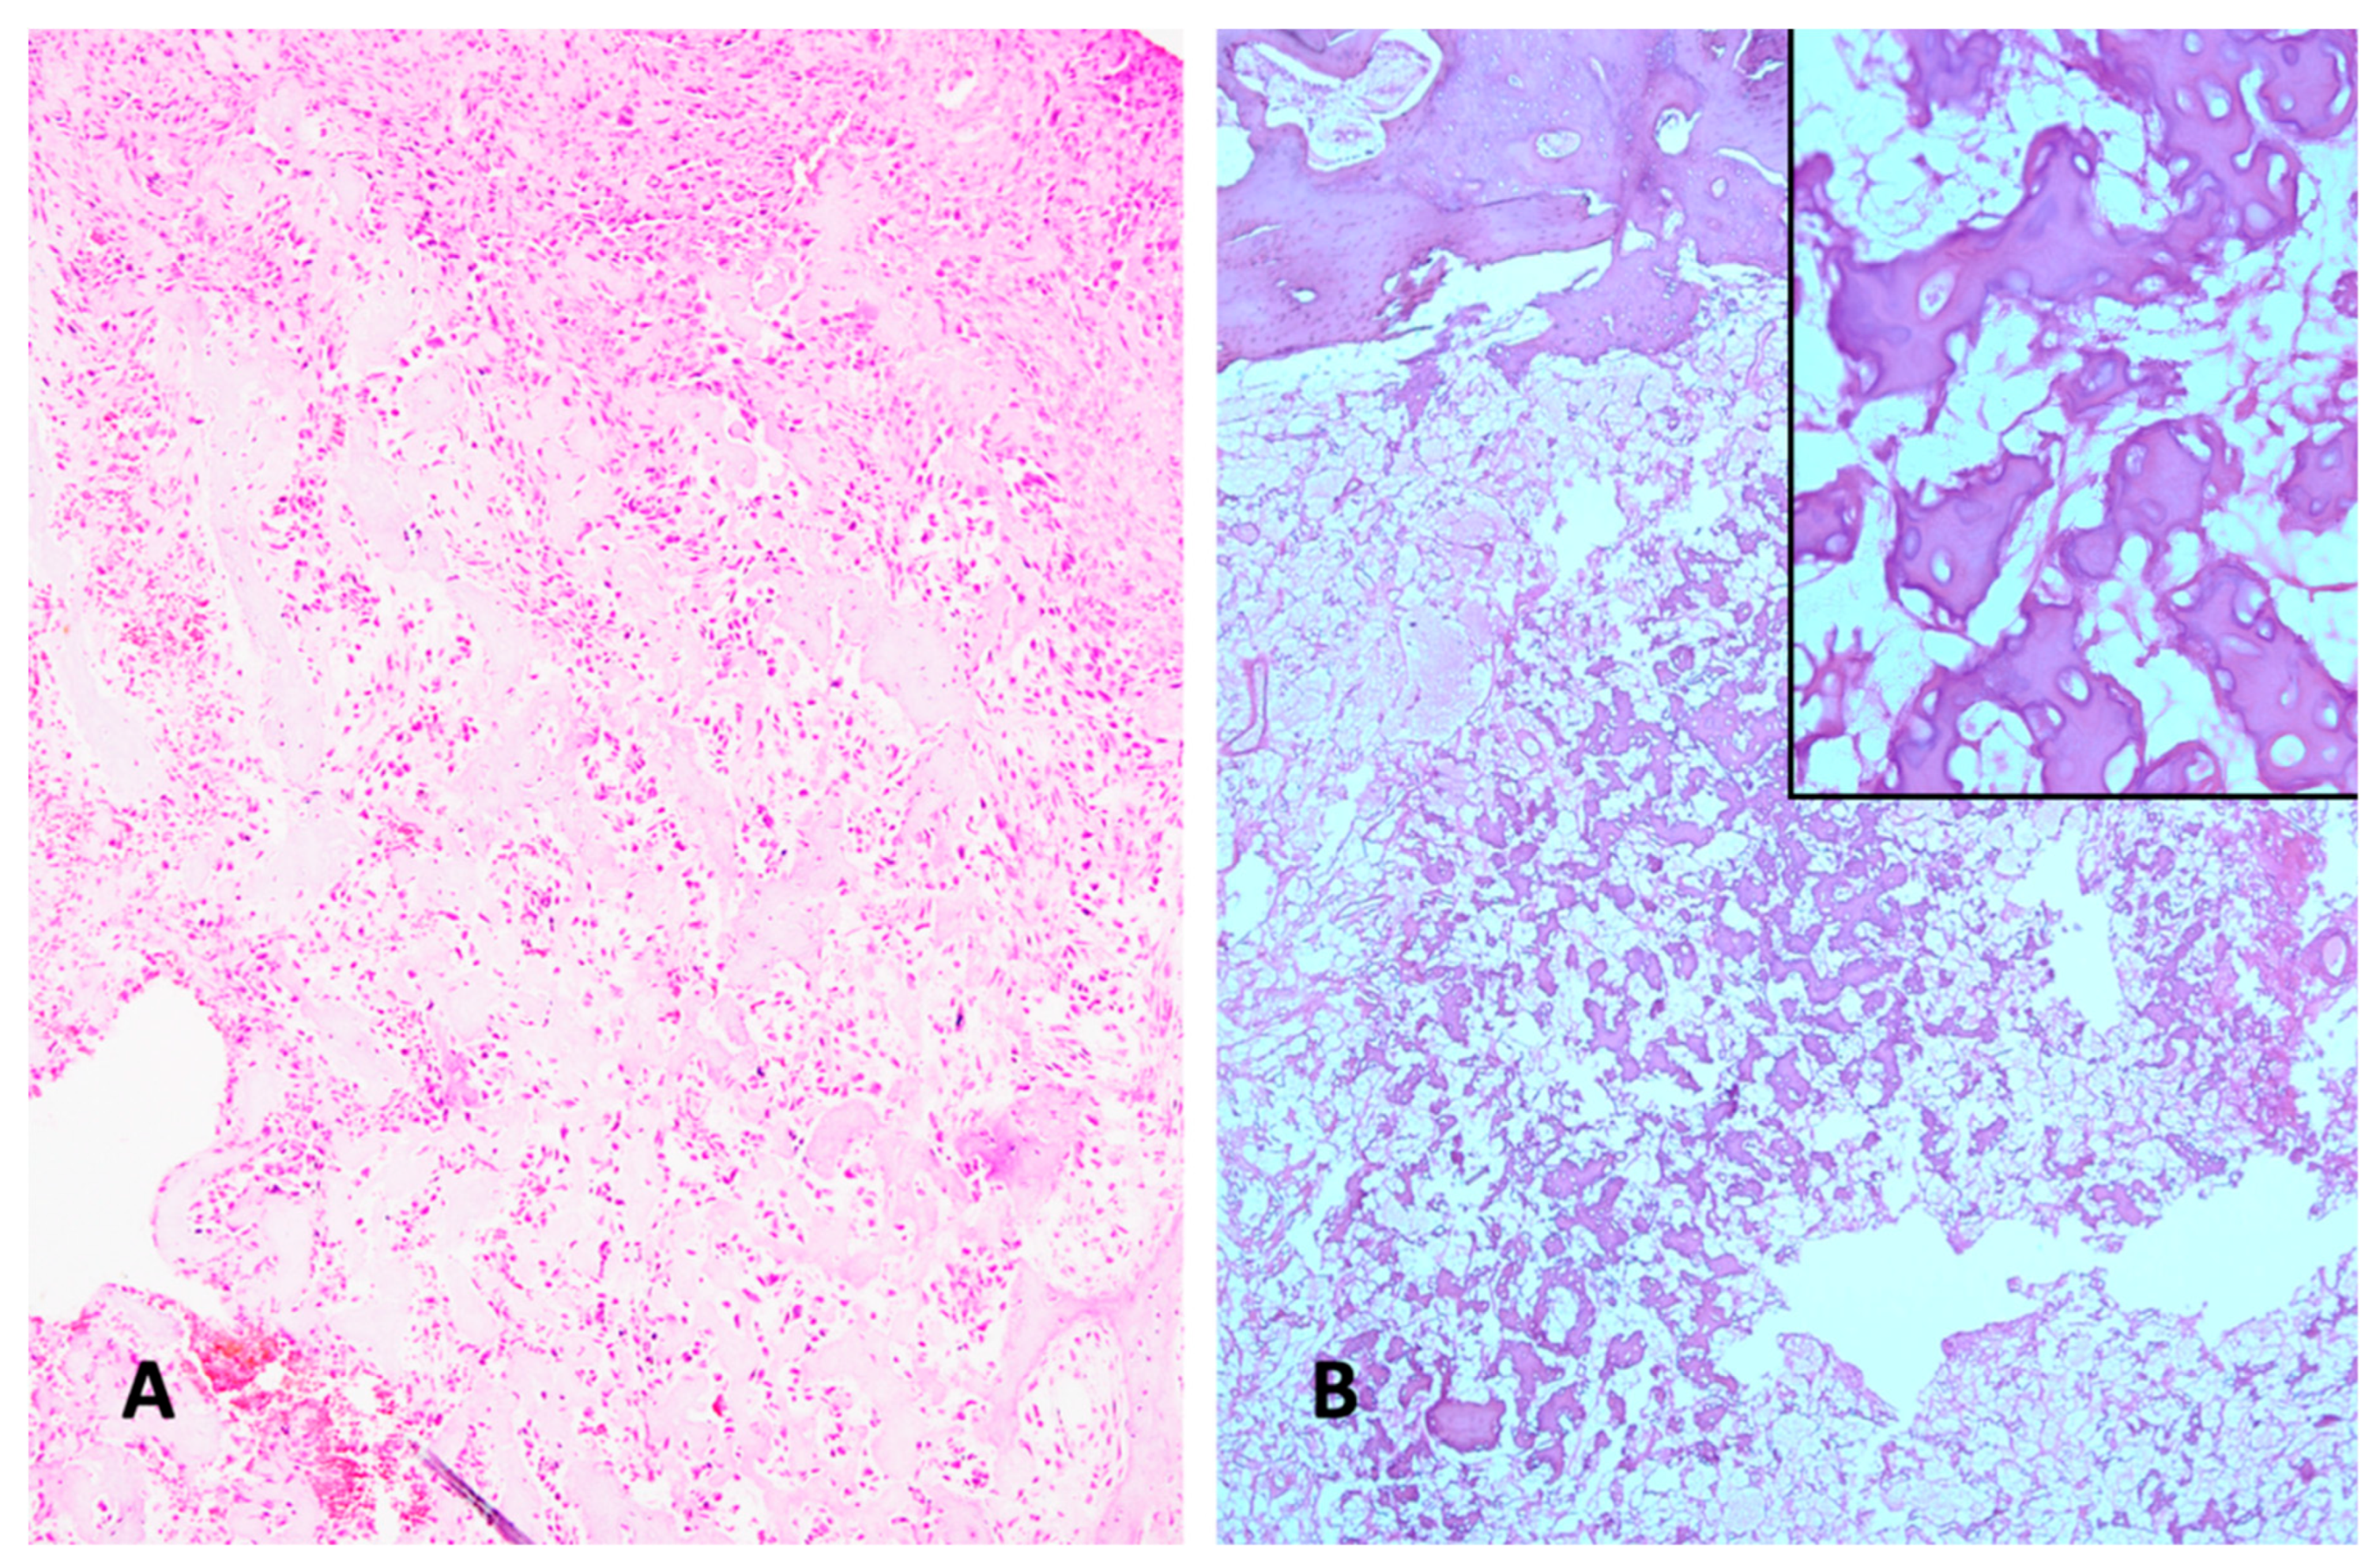

2. Histologic Characteristics

- Klein, M.J.; Siegal, G.P. Osteosarcoma. Am. J. Clin. Pathol. 2006, 125, 555–581. [Google Scholar] [CrossRef]

- Chui, M.H.; Kandel, R.A.; Wong, M.; Griffin, A.M.; Bell, R.S.; Blackstein, M.E.; Wunder, J.S.; Dickson, B.C.; Michael Herman Chui, MD; Rita A. Kandel, MD; Marcus Wong, BSc; Anthony M. Griffin, MSc; Robert S. Bell, MD; Martin E. Blackstein, MD, PhD; Jay S. Wunder, MD, MSc; Brendan C. Dickson, MD, MScFrom the Departments of Pathology and Laboratory Medicine; Md; et al. Histopathologic Features of Prognostic Significance in High-Grade Osteosarcoma. Arch. Pathol. Lab. Med. 2016, 140, 1231–1242. [Google Scholar] [CrossRef]